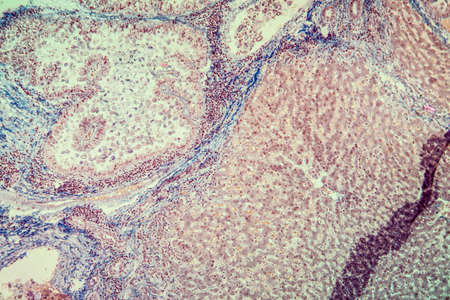

Bowen's Disease Tumor under the microscope 100x

Bowen's Disease Tumor under the microscope 100x